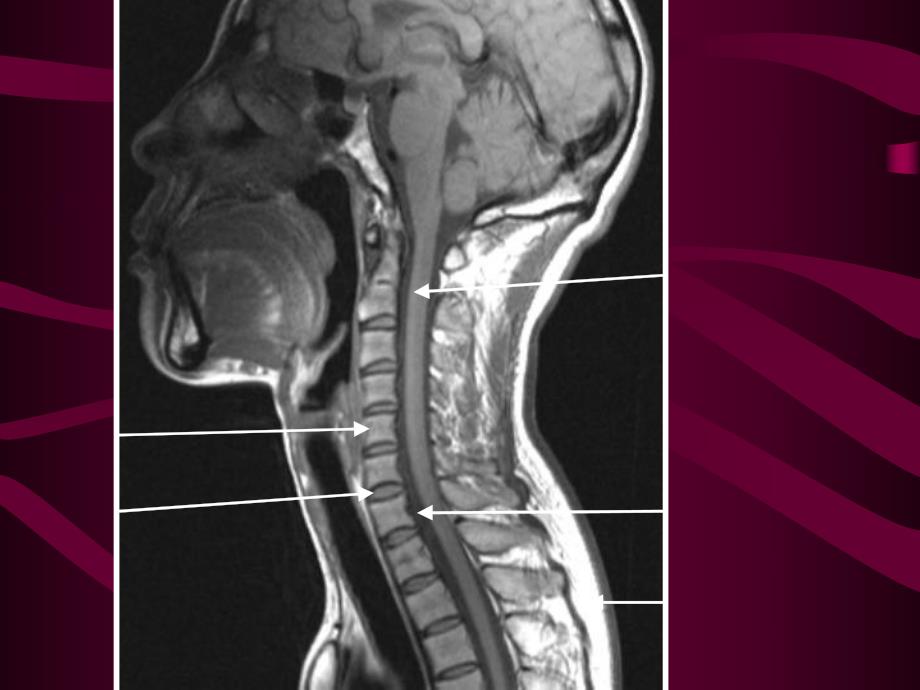

1、第六节第六节 脊髓和椎管内疾病脊髓和椎管内疾病MR诊断诊断正常脊柱的扫描系列及表现正常脊柱的扫描系列及表现 Sag-T1WI,矢状位T1加权序列具有成像速度快,定位简单的优势。在该序列上,骨皮质、韧带、蛛网膜下腔呈低信号,骨髓呈中等偏高信号,椎间盘呈中等信号,信号强度低于椎体,脂肪呈高信号,肌纤维间隙因为脂肪的存在而呈高信号,本序列在正常解剖显示上有优势本序列在正常解剖显示上有优势。Sag-T2WI,矢状位T2加权序列上,骨皮质、韧带呈低信号,骨髓呈中等偏高信号,椎间盘(髓核及内纤维环的信号较外纤维环高)呈中等信号,信号强度高于椎体,蛛网膜下腔、脂肪呈高信号,本序列对于椎间盘、脊髓病变的显示很

2、本序列对于椎间盘、脊髓病变的显示很大的有优势大的有优势,是临床,是临床最常用的序列最常用的序列。Ax-T2WI,轴位T2加权序列上。本序列在本序列在椎间盘病变及椎间盘病变及椎管内占位病变定位上有很椎管内占位病变定位上有很大的优势大的优势。STIR(Fs T2WI)脂肪抑制T2加权,主要用于观察椎体病变主要用于观察椎体病变 椎管内肿瘤的分类 髓内肿瘤髓内肿瘤 室管膜瘤室管膜瘤 星形细胞瘤星形细胞瘤 髓外硬膜内肿瘤髓外硬膜内肿瘤 神经鞘瘤神经鞘瘤 脊膜瘤脊膜瘤 硬膜外肿瘤硬膜外肿瘤 转移瘤转移瘤 淋巴瘤淋巴瘤 脊柱和椎管内肿瘤 髓内肿瘤定位:脊髓增粗,蛛网膜下腔变窄。室管膜瘤、星形细胞瘤、血管母细